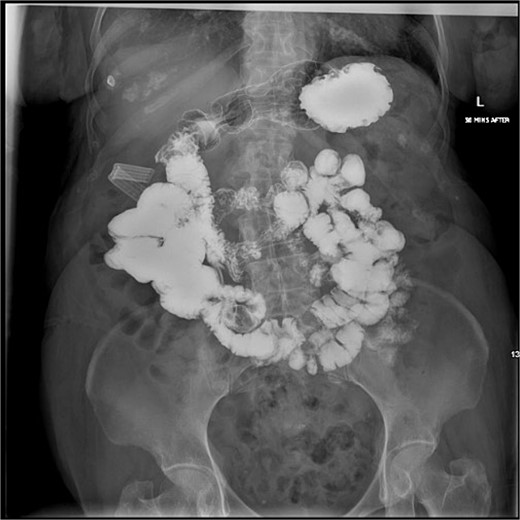

She tolerated the procedure well, and was started on sips with oral medications on postoperative day 1. On postoperative day 4, an upper gastrointestinal study showed normal passage of contrast from the stomach, through the duodenum, and beyond without leakage of contrast (Fig. 6). Her drain was removed and she was discharged home on a regular diet on postoperative day 7.

Postoperative upper gastrointestinal study. The postoperative upper gastrointestinal study showed flow through the duodenum without contrast leakage.